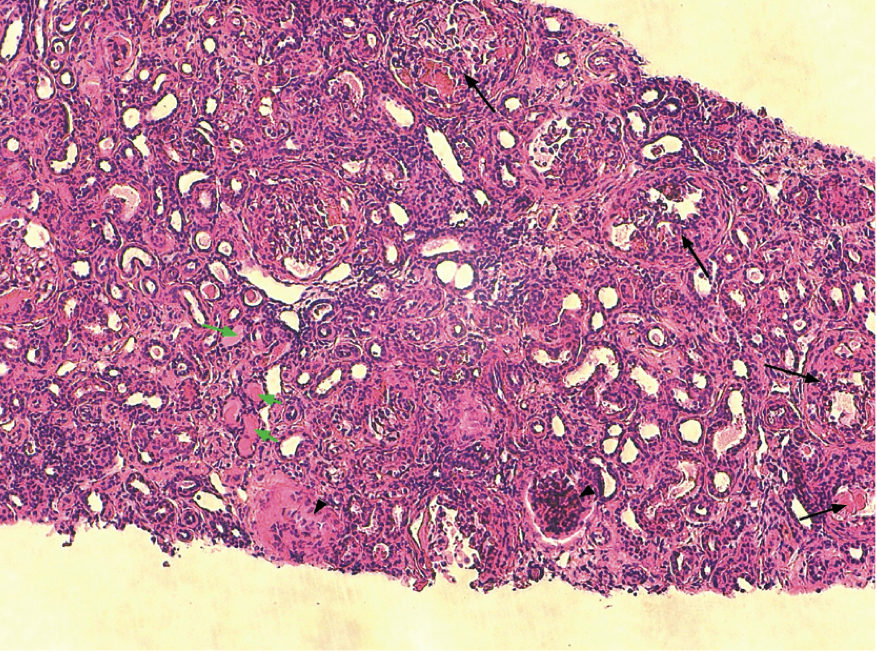

Histologie : l’analyse de deux biopsies de petite taille permet la visualisation d’une dizaine de glomérules rénaux. On note une atteinte glomérulaire avec fibrose segmentaire et adhérence à la capsule de Bowman, quelques images de croissant glomérulaire et de glomérulosclérose associée à des lésions discrètes de néphrite interstitielle lympho-plasmocytaire avec fibroplasie marquée, atrophie tubulaire marquée et protéinurie. Ces images histologiques sont évocatrices d’une néphropathie familiale dans le contexte clinique actuel (photo 4).

Photo 4 : Atteinte glomérulaire majeure avec fibrose segmentaire et adhérence à la capsule de Bowman (flèche noire), glomérulosclérose (tête de flèche) et protéinurie (flèche vertes)(photo Dr M. Fine).

La gravité des lésions histologiques rénales observées dépend du stade de progression de la maladie. Les lésions discrètes montrent un épaississement segmentaire avec un aspect « mité » de la membrane basale des capillaires glomérulaires. Les lésions modérées montrent une fibrose glomérulaire segmentaire avec adhérence à la capsule de Bowman associée à une fibrose périglomérulaire. Les lésions évoluées sont une glomérulosclérose avec ou sans dilatation kystique de la chambre glomérulaire. il s’y ajoute des lésions de fibrose interstitielle avec infiltrat lympho-plasmocytaire multifocal, nécrose, fibrose ou dilatation tubulaire et protéinurie (1) (4).